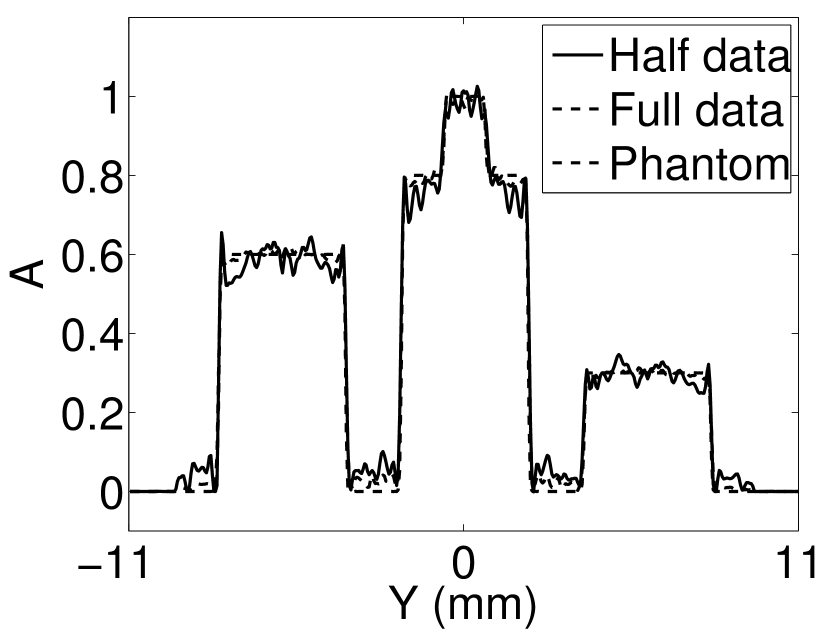

Figure 2(a) shows the image reconstructed by use of the conventional iterative method that utilized a system matrix based on EIR-2. Different values of the regularization parameter from the interval were considered. The reconstructed image with the value of that minimized the RMSE was chosen to represent the best performance of the conventional iterative method. Figure 2(a) and the profile in Figure 2(c) demonstrate that the use of an inaccurate EIR can result in strong artifacts and distortions in images reconstructed by use of the conventional methods.

When the VP algorithm was applied, different values of the regularization parameter from the interval and from the interval were considered. The image that minimized the RMSE was chosen and displayed in Figure 2(b). As revealed by this image and the profiles in 2(c), the VP algorithm yielded an image with fewer artifacts and distortions, and image fidelity was improved as reflected by the reduced RMSE.

V-A3 Effect of data incompleteness

Incomplete, or sparsely sampled, data sets are sometimes acquired in practice. To study the effect of data incompleteness on the VP algorithm, we reconstructed images from data corresponding to half of the equally spaced transducers (). Because the data were noiseless, no explicit regularization was employed () in the conventional reconstruction algorithm. However, the explicit regularization was still employed in the VP algorithm because of the ill-posed nature of the joint reconstruction problem. The results are shown in Figure 5. As expected, use of the incomplete data set resulted in less accurate reconstructed images for both the conventional iterative reconstruction method and the VP algorithm. However, this effect was more pronounced for the VP algorithm. Note that for the VP algorithm, larger values of the regularization parameters were applied when the incomplete data set was employed than when the complete data set was employed (Figure 5(h) and 5(g)).